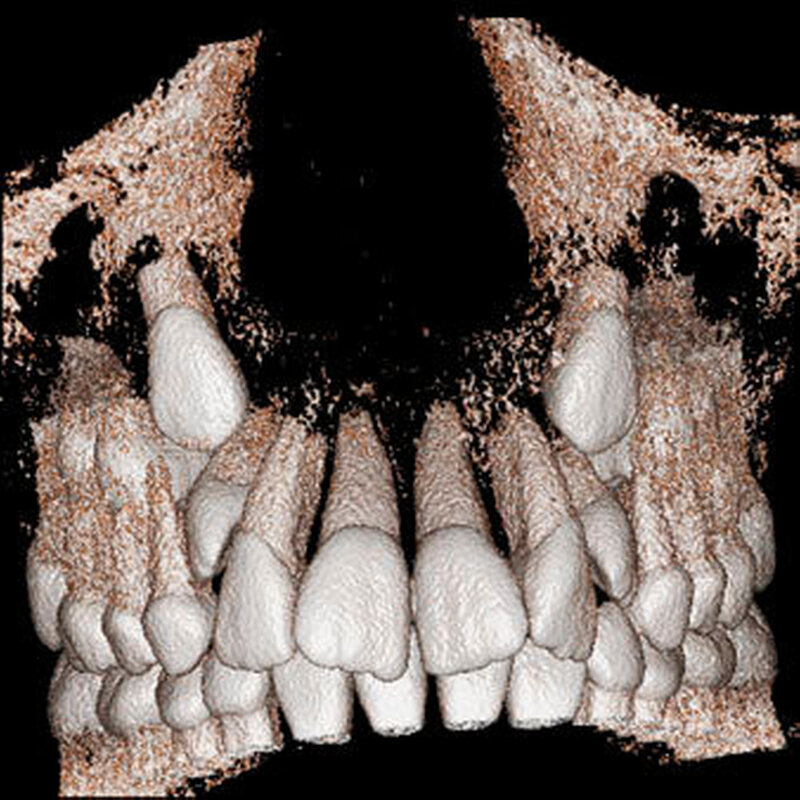

Bei überzähligen Zähnen werden vier morphologische Typen unterschieden: konisch (Abbildung 9), tuberkulär (höckerförmig; Abbildung 10), überzählige Zähne mit identischer Zahnform (Abbildung 11) und Odontom (Abbildung 12) [GARVEY et al. 1999]. Der konische überzählige Zahn ist ein kleiner, zapfenförmiger Zahn und zudem der häufigste Fall im bleibenden Gebiss [Rajab Hamdan 2002, Liu et al. 2007, Gündüz et al., 2008; Ferrés-Padró et al., 2009; Hyun et al., 2009; Schmuckli et al., 2010; Mossaz et al., 2014]. Er kommt oft zwischen den oberen zentralen Schneidezähnen vor und entwickelt sich gleichzeitig zur Wurzelbildung der bleibenden Schneidezähne. Konische überzählige Zähne führen meist nicht zu einer Durchbruchstörung oder -behinderung der zentralen Schneidezähne. Tuberkuläre, überzählige Zähne sind größer als der konische Typ und besitzen einen zusätzlichen charakteristischen Höcker oder Tuberkel der Zahnkrone. Sie kommen oft gepaart vor und liegen in der Regel palatinal der oberen mittleren Schneidezähne. Im Gegensatz zu konischen überzähligen Zähnen brechen die meisten tuberkulären nicht in die Mundhöhle durch und es kommt nicht selten zur Durchbruchstörung oder -behinderung der zentralen Schneidezähne [Mason et al., 2000; Minguez-Martinez et al., 2012]. Überzählige Zähne mit identischer Zahnform sind Zähne, welche vom eigentlichen Zahn in der Lage (also in der Zahnreihe gelegen) und Form nicht zu unterscheiden sind.

Die überzähligen Zähne mit identischer Zahnform finden sich normalerweise beim oberen seitlichen Schneidezahn. Zusätzliche Prämolaren und Molaren können aber auch auftreten. Die Mehrheit der überzähligen Zähne im Milchgebiss sind vom identischen Zahnform-Typ und bleiben nur selten impaktiert oder retiniert.